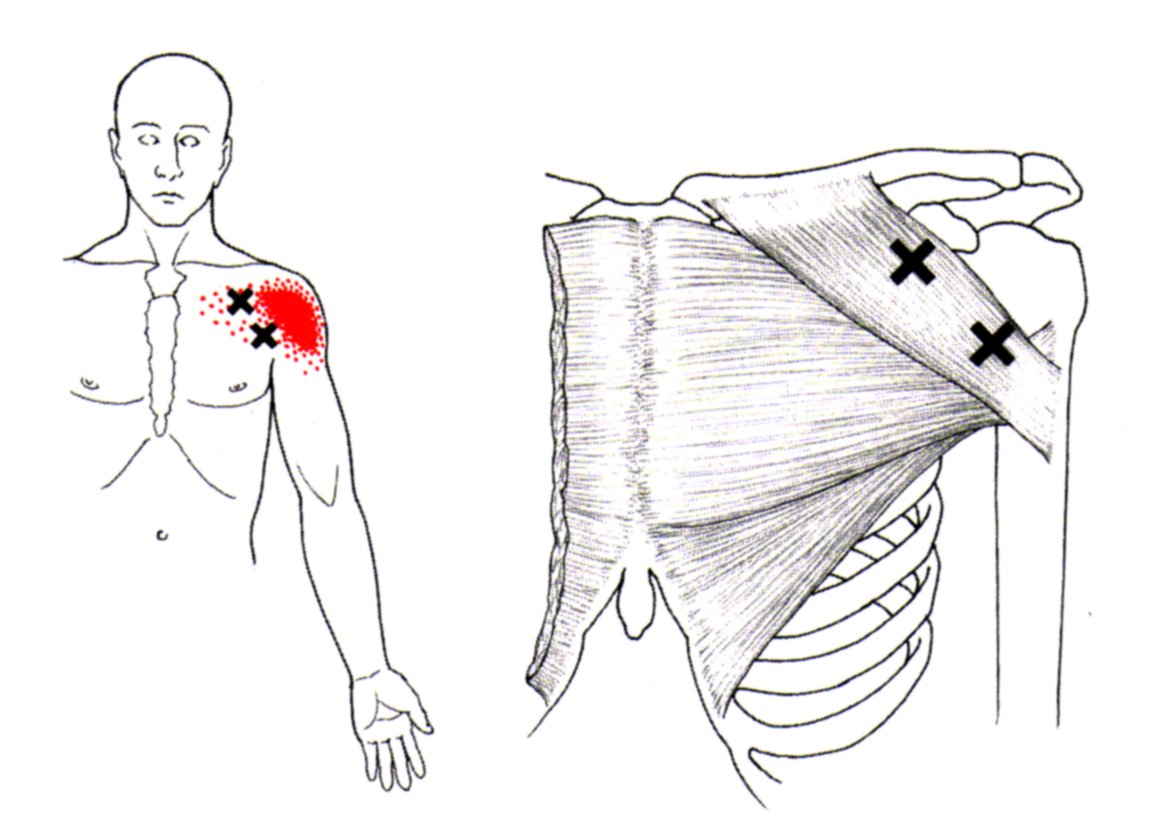

육.트리거 포인트

통증 유발점은 통증과 불편함을 유발하는 근육 긴장 또는 과사용 영역입니다. 대흉근도 예외는 아니며 신체의 다른 부분에 통증을 유발하는 통증유발점을 만들 수 있습니다.

대흉근의 통증유발점은 일반적으로 흉골에 부착되는 근육의 흉골 부분에 있습니다. 이러한 통증유발점은 가슴, 어깨, 팔에 통증과 불편함을 유발할 수 있습니다.

통증 유발점이 대흉근에 있을 때 신체의 다른 곳에서 느낄 수 있는 연관통을 유발합니다. 통증은 어깨, 팔 또는 손으로 퍼질 수 있습니다.

대흉근의 통증유발점은 과도한 사용, 부상, 잘못된 자세 등 다양한 요인으로 인해 발생할 수 있습니다. 통증유발점 마사지, 스트레칭, 근력운동 등으로 치료할 수 있습니다. 더 이상의 통증과 불편함을 유발하지 않도록 대흉근 통증유발점에 대한 치료를 찾는 것이 중요합니다.